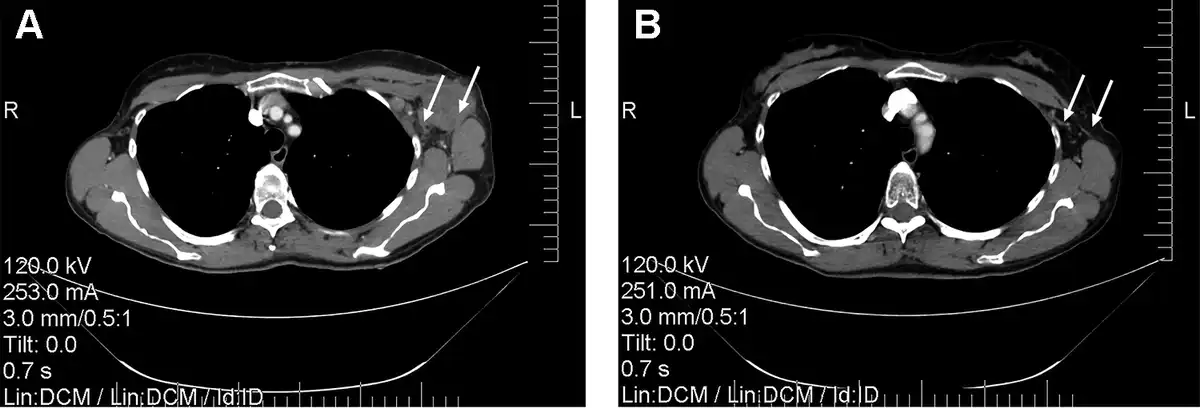

There were no significant differences in the size of regional lymph nodes between the 2 groups prior to any treatment procedures. The combination of NACT and RIMH showed a decrease of 7.67 mm (32.08 ± 4.13)% in the size of the involved lymph nodes, whereas BC patients given NACT alone had a 5.79 mm (17.91 ± 4.35)% reduction on average. Figure 6 presents a typical case of the lymph node reduction in a BC patient treated with NACT + RIMH. There was a 14.17% difference in the treatment response of axillary lymph node metastasis between NACT followed by RIMH and NACT alone (p = 0.011).

Figure 6

Computed tomography scans of the chest showing reduction of axillary lymph node metastasis in a 47-year-old patient who received NACT combined with RIMH: A—before combined treatment; B—after combined treatment. White arrows indicate axillary lymph node metastasis. Abbreviation: NACT, Neoadjuvant chemotherapy; RIMH, Regional inductive moderate hyperthermia.